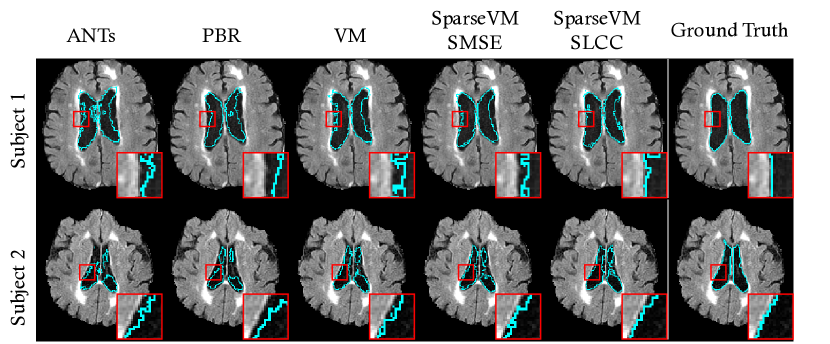

Since the registration results across subjects exhibit high variance, as shown by the standard deviations, we show the Dice score for each subject in Figure 3. SparseVM using SLCC outperforms the much slower ANTs on 86.7% of test subjects and the much slower PBR on 69.3% of test subjects. It has higher accuracy than VoxelMorph on 90.7% of test subjects. We show two example of subject registration results in Figure 2. This figure shows a warped atlas segmentation overlaid on a test subject scan for each method. We highlight that these overlaid images are useful for qualitatively showing the accuracy of the resulting flow fields, but the flow fields themselves are the clinically important output. The close-up view in Figure 2 shows that the warped segmentation from our method snaps to edges well. This means that the flow fields produced by our method are accurate near anatomical boundaries.